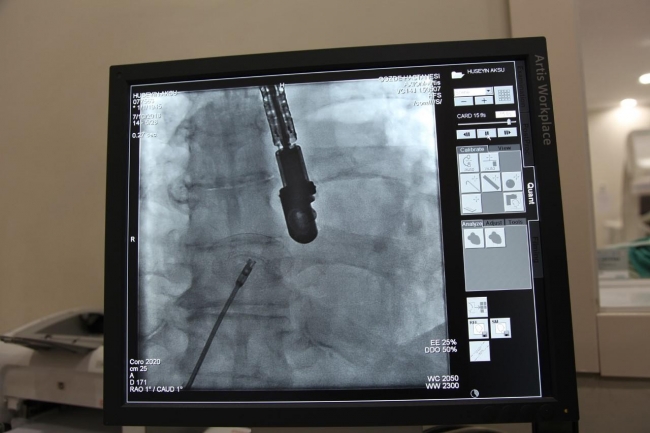

Malatya'da 80 yaşındaki Hasan Örnek'in kalbinde doğuştan delik olduğu, yorgunluk ve nefes darlığı şikayetiyle başvurduğu hastanede fark edildi. Tetkiklerinde kalbinde doğuştan 1,8 santim büyüklüğünde delik olduğu tespit edilen Örmek, Kardiyoloji Uzmanları Prof. Dr. İzzet Tandoğan ve Uzm. Dr. Sezai Orhan tarafından ameliyata alındı. Kapalı yöntemle geçirdiği ameliyat sonrası yaşlı hasta sağlığına kavuştu.

Kardiyoloji Uzmanı Prof. Dr. İzzet Tandoğan, hastada bir anormallik saptadıklarını belirterek "Kalbin içerisindeki delik, normalde anne karnındayken olabilen fakat doğuma kadar kapanan bir deliktir. Normal şartlarda biz böyle hastalarla karşılaşıyoruz ama 10 ya da 20’li yaşlara kadar karşılaşıyoruz. O yaşlara kadar bu hastalar tedavi edilmemişse kalp yetmezliği başlıyor. Hastamızın 80 yaşına kadar kalbindeki delikle yaşaması bir hayli ilginç. Biz, 80 yaşındaki bir hastamıza ilk defa bu işlemi uyguladık. Çünkü ilk defa 80 yaşında ve kalbi bir delik hasta gördük. Başarılı bir operasyonla hastamız sağlığına kavuştu" dedi.